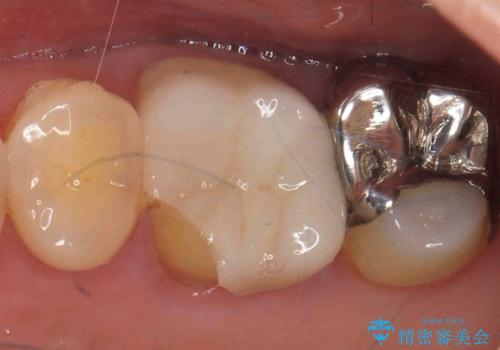

割れた被せ物を作りなおしたい

- 他院で装着した被せ物が割れたとのことで来院されました。

被せ物の厚みが確保されていなかったため、向かいの歯とのスペースを確保するように修正していきます。

被せ物の厚みが十分に確保できていないと、材料によっては今回のように割れてしまうことがあります。

被せ物の材料を変えるか、厚みを確保することでそのリスクを抑えることができます。

今回はセラミックでの再治療をご希望されたため被せ物の厚みを確保することで対応しました。